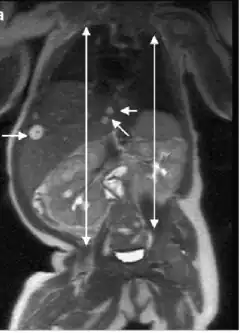

MRI shows the multiple hyperintense hepatic lesions , observe the right hemihypertrophy in this newborn with Beckwith-Wiedemann syndrome

The evaluation of Beckwith-Wiedemann syndrome is based on clinical presentation and genetic test[21]